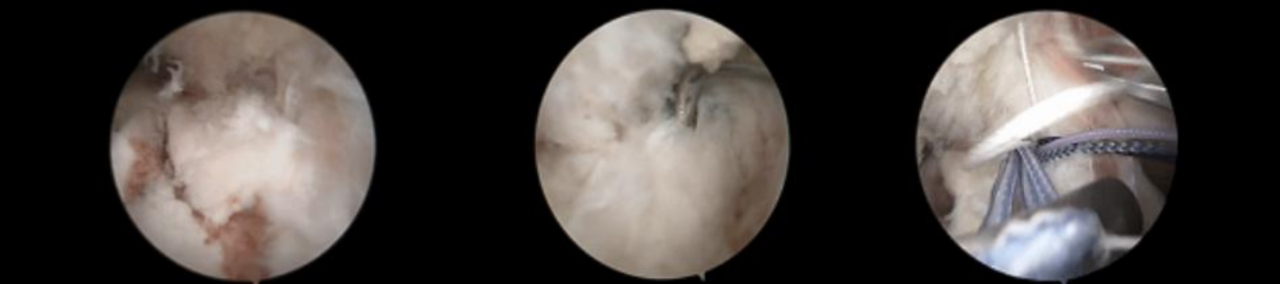

分型及术式

ⅢB型:多块撕脱骨折;合并半月板撕裂;BC>15mm;AE/AD≥1/2。

术式: 双袢(后叉前建立骨道)+骨道固定

合并内侧半月板放射裂

撕脱骨折、内侧半月板放射裂

半月板骨道固定、双袢固定撕脱骨折

术后X线片